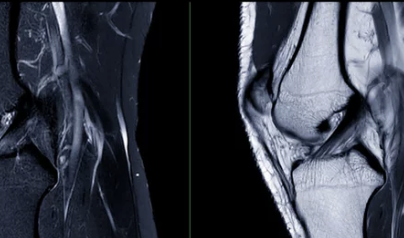

5. 무릎에 물이 차는 대표적인 원인

무릎에 물이 차는 이유는 하나가 아닙니다.

흔한 원인들

- 퇴행성 관절염

- 반월상연골판 손상

- 인대 손상

- 활액막염

- 외상 후 염증

- 통풍, 류마티스 질환